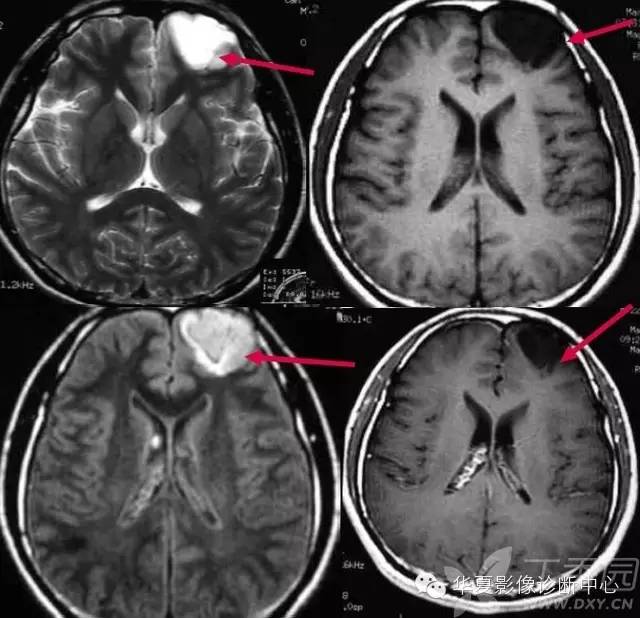

常春藤征

该征是指烟雾病患者MR检查增强扫描时图像上观察到沿柔脑膜分布的点状或线状强化信号影,因类似爬行在石头上的常春藤而命名。文献报道这种征象出现率约70%,并提出其对烟雾病的诊断具有特异性。其形成主要是双侧颈内动脉、大脑前、中动脉狭窄或闭塞后,颈外动脉及椎-基底动脉系统参与代偿性供血的侧支循环血管,包括大脑后动脉、脑膜中动脉、颞浅动脉、枕动脉,沿双侧大脑皮层柔脑膜分布。有研究报道FLAIR图像亦可观察到常春藤征,表现为柔脑膜弥漫性高信号改变。FLAIR序列是水信号为零时的反转脉冲序列,由于FLAIR能够有效地克服脑脊液在T2WI呈高信号所致的部分容积效应和伪影的影响,敏感地反映蛛网膜下腔轻微信号强度的改变,对蛛网膜下腔病变如蛛网膜下腔出血、脑膜炎和脑膜转移瘤等比常规T2WI敏感。在烟雾病患者FLAIR图像上的常春藤征的产生机制仍未完全清楚,目前存在几种不同的说法:

1)脑底异常血管网和脑表面代偿性侧支循环血管与柔脑膜血管吻合,形成皮层柔脑膜侧支血管网,由于其血流速度缓慢,而表现为高信号;

2)皮层软脑膜侧支吻合血管网的柔脑膜动脉扩张;

3)皮层柔脑膜充血、水肿、增厚。有研究者观察到有效的血管重建术后烟雾血管和皮层柔脑膜点状或线状高信号减少甚至消失,患者临床症状明显改善,提示FLAIR图像上柔脑膜点状或线状高信号信号改变为皮层柔脑膜血管充血、水肿和增厚。

这种表现是由于颈内动脉及大脑中动脉狭窄、闭塞后,颈外动脉及椎-基底动脉系统参与代偿性供血,通过DSA检查可见扩张的颈外动脉系统及大脑后动脉参与形成的柔脑膜侧支血管网,颈内动脉狭窄或闭塞程度越严重,柔脑膜高信号的范围越广泛,其常春藤征表现越明显。常春藤征的轻重与病情进展情况有关。根据DSA表现,烟雾病的病程分为6个阶段: